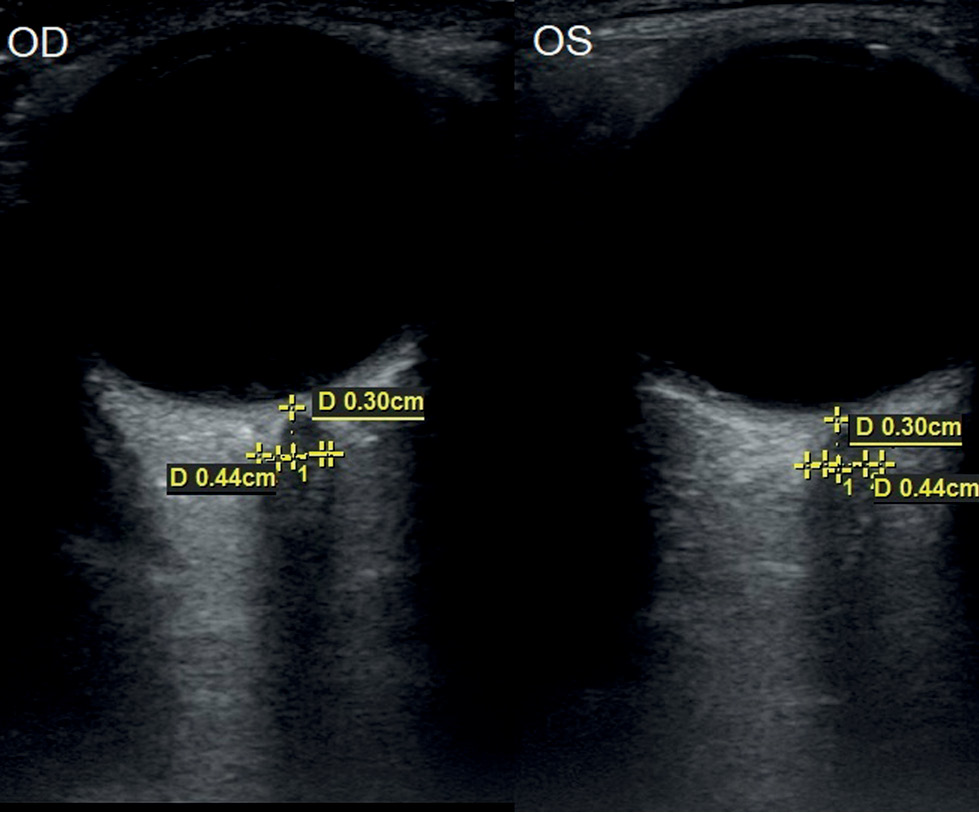

У 32 детей (64 глаза) с гипоплазией зрительного нерва наблюдалось значительное уменьшение показателя ТОЗН по сравнению с контролем во всех возрастных группах (р <0,05) (табл. 1, рис 3, 4).

Рис. 4. Эхограмма при гипоплазии зрительного нерва обоих глаз у мальчика в возрасте 8 лет. Биометрические показатели ретробульбарного отдела зрительного нерва правого (OD) и левого (OS) глаза.

Fig. 4. Echogram of optic nerve hypoplasia in both eyes of an 8-year-old boy and biometric data of the retrobulbar optic nerve of the right (OD) and left (OS) eyes.